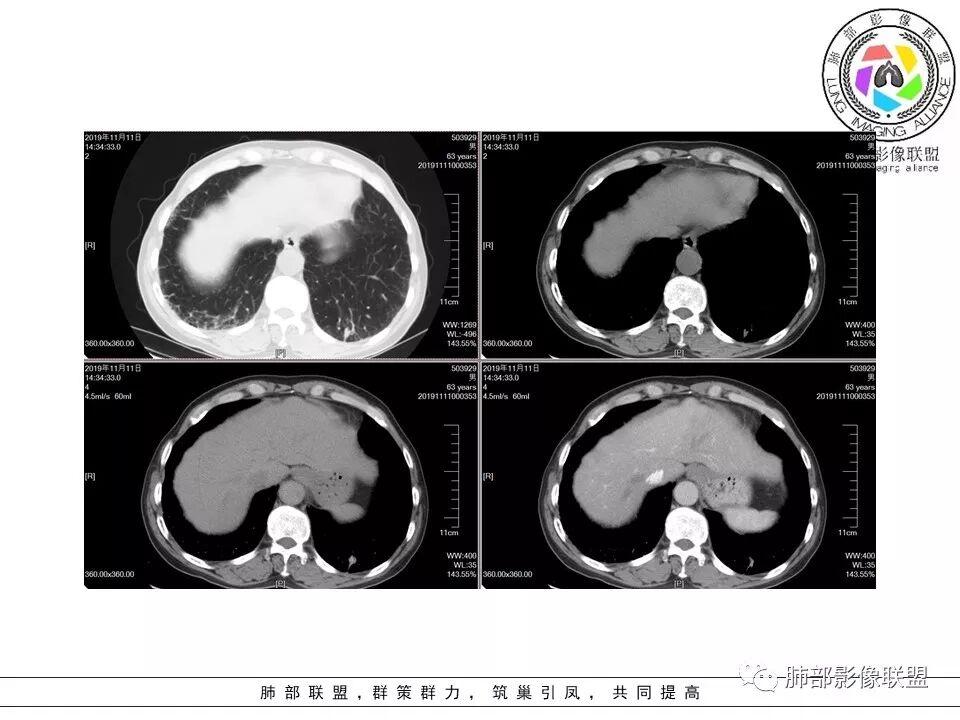

大雄:老年男性,有类风湿病史,长期服用激素,无阳性主诉CT示右肺上叶后段及左肺下叶基底段胸膜下多结节影,境界清晰,边缘毛糙,整体收缩,长轴与胸膜平行,增强扫描轻中度均匀强化。考虑炎性病变,建议查隐球荚膜多糖滴度试验

晕晕菜:患者中老年男性,体检发现肺部占位。既往既往有类风湿关节炎,长期口服激素胸CT:间隔旁肺气肿,右肺上叶后段胸膜下病变,与胸膜宽基底相连,局部胸膜明显增厚,病灶内可见空洞,病灶周围有散在卫星灶。左肺下叶背段胸膜下实变,病灶边界清楚,与长轴与胸膜平行,病灶周围可见软毛刺,纵隔窗可见病灶与胸膜呈糊墙征。 总体考虑良性病变。右上:结核?左下:隐球菌?

没意见:老年男性,明确有风免疾病背景,长期激素治疗,CT:双肺下叶外周多发结节,大部分宽基底胸膜相连,长轴垂直支气管,刀切平直,密度较为均匀,近心端空洞,强化程度目测略低,下肺背侧网格、磨玻璃、小蜂窝,考虑炎性结节,至于是感染还是风湿结节难度较大,需要结合临床来进一步确认

小赵:老年男性,类风湿及长期服药史。胸部CT所见右肺上叶及左肺下叶胸膜下多发病灶,右肺上叶病灶内见空洞及液平面,内壁光滑,周围散在条索及小结节样卫星灶,邻近胸膜增厚,增强扫描病灶轻度强化。左肺下叶病灶长轴平行于胸膜,周围见边界不清磨玻璃密度影,与邻近胸膜成糊墙改变。增强扫描病变成不均匀明显强化,内见强化血管影。诊断一元考虑双肺炎性病变,隐球菌可能。二元考虑右肺上叶结核,左肺下叶隐球菌感染,粘液腺癌待排。

菲菲菲:男,63,体检发现肺占位,既往类风湿性关节炎13年,双肺胸膜下多发斑片及结节影,右肺下叶病灶内见偏心性小空洞形成,周围有卫星灶,胸膜增厚,左肺下叶病灶轻度强化,纵隔内无肿大淋巴结,考虑炎性病变。隐球菌鉴别结核

破风5:胸部CT:右上叶胸膜下病变,与胸膜宽基底相连,累及胸膜,病灶内可见空洞,洞壁光滑,病灶周围有散在卫星灶。有类风湿激素口服历史,结核首先考虑。左肺下叶背段胸膜下实变,病灶边界清楚,与长轴与胸膜平行,血管伸入,纵隔窗可见糊墙征。考虑良性病变,隐球?总体,右上肺结核,左下肺隐球,CTD-ILD

流心明智:患者,老年男性,既往有类风湿关节炎,长期口服激素史。胸CT:间隔旁肺气肿,右肺上叶后段胸膜下病变,与胸膜宽基底相连,局部胸膜增厚,病灶内向肺门侧空洞,病灶周围卫星灶。考虑炎性病灶。左肺下叶胸膜下气肿背景边缘实变、边界清楚、有膨隆、滋养血管征,软毛刺、多结节融合、糊墙征。 总体考虑:良性病变,右上:结核?左下:隐球菌?左下鉴别Ca。

傅昌瑜:男,63,体检发现肺占位,既往类风湿性关节炎13年,RF升高,右下肺胸膜下结节,边缘多发斑片,右肺下叶病灶内见偏心性小空洞形成,相应层面胸膜增厚,左肺下叶两个结节,上面大点的结节位于胸膜下,似有支气管进入后截断,病灶轻度强化,病灶内见坏死区,纵隔内无肿大淋巴结。肺内病灶似乎不怎么类似,隐球菌应该是兄弟同心。肺内病灶考虑肉芽肿性病灶,有长期口服糖皮质激素史,首先考虑奴卡可能,鉴别隐球菌及结核这个妖怪。类风湿结节没有见过。

果哣.:老年男性,有免疫抑制服药史,右肺上叶后段胸膜下一节结影,内有空洞靠近肺门,周围散在小叶中心结节,左肺下叶靠近胸膜一节结影,长轴垂直支气管,糊墙,轻度强化,考虑结核,隐球菌带排。